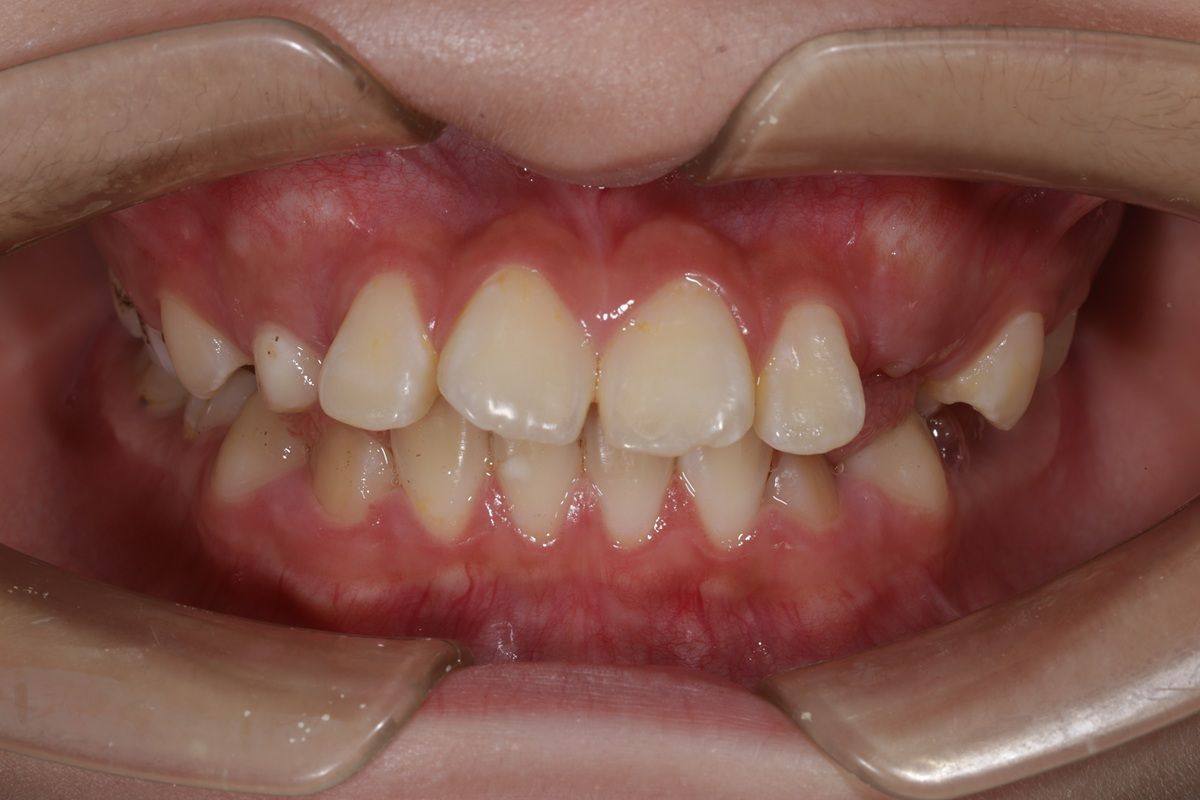

1 Tình trạng răng trước khi niềng

Sau khi thăm khám tại Nha khoa Hanseoul, bác sĩ ghi nhận các vấn đề chính của Võ Đức Kiên:

Răng cửa trên khấp khểnh, chìa ra ngoài.

Răng mọc lệch, chen chúc, thiếu khoảng sắp xếp.

Khớp cắn sai lệch, ảnh hưởng đến thẩm mỹ và chức năng ăn nhai.